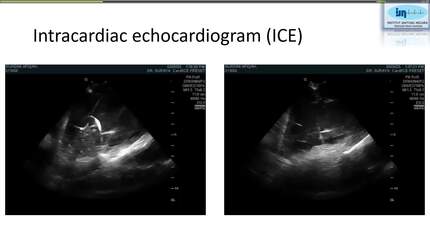

Fluoroless dual-chamber pacemaker implantation in a pregnant woman with ventricular standstill